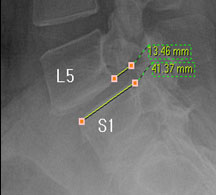

즉, 척추전방위증은 통증을 일으키는 원인질환(디스크, 협착증)을 치료하는 것이 척추 뼈를 더 이상 앞으로 밀려나가지 않게 하는 치료라고 볼 수 있습니다. 모커리는 뼈가 50% 이상 밀려나간 2단계의 척추전방위증도 비수술로 치료하고 있으며, 이러한 한방치료 효과를 객관적으로 검증하여 유명학회 및 논문에 계속해서 발표하고 있습니다.

모커리한방병원은 50% 정도 밀려나간 2단계의 척추전방위증 환자를 대상으로 약 3주간의 입원집중치료를 실시한 결과, 입원 시보다 80% 이상 통증이 감소되어 치료되었습니다. 통증 없이 걷는 시간도 약 3배 정도 증가되어 단기간에 수술 없이 높은 치료효과가 나타났다는 것을 대한침구의학회에 발표하였습니다. 50% 정도 밀려나간 2단계의 중증 척추전방전위증 환자이면서 심한 척추협착증 증상을 나타내는 환자를 치료한 결과입니다.